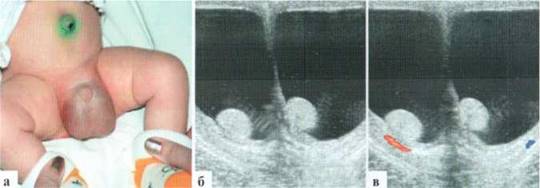

Трансформация гидатиды у детей является наиболее частой причиной развития СОМ. Причины возникновения этой патологии не всегда понятны, однозначного мнения о генезе заболевания в настоящий момент нет. Возможен как механический перекрут ножки гидатиды, так и ее инфаркт по невыясненным причинам. Гидатида значительно увеличивается в размерах, часто приобретает «ячеистую» структуру. Форма трансформированной гидатиды обычно округлая или овальная. Размеры чаще от 3x3 до 5x6 мм. При допплеровском исследовании трансформированная гидатита всегда аваскулярна (2.1.1).

Рис. 2.1.1. Трансформация гидатиды:

а — внешний вид пациента; б, в — гидатида (пунктир) у верхнего полюса яичка